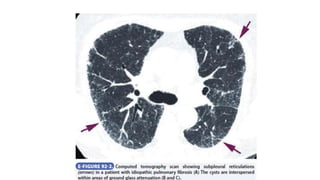

• Chest radiographs typically show basal-predominant reticular

abnormalities with low lung volumes.

• The diagnostic features on HRCT are peripheral, predominantly basilar

patchy intralobular reticulation, often with subpleural honeycomb

cysts, traction bronchiectasis, and traction bronchiectasis as the

disease becomes more advanced.

• HRCT reveals a predominant ground-glass pattern of attenuation,

usually bilateral and often associated with subpleural reticulation,

and loss of volume in the lower lobe.

• In cellular nonspecific interstitial pneumonia, HRCT shows ground-

glass opacification, consolidation, or both, but the biopsy shows mild

to moderate lymphoplasmacytic interstitial chronic inflammation.

• In contrast, fibrotic nonspecific interstitial pneumonia has a bilateral

lower lobe distribution with architectural derangement on HRCT;

histopathologically, it has uniformly dense interstitial fibrosis and may

sometimes be difficult to distinguish from idiopathic pulmonary

fibrosis and usual interstitial pneumonia in the early clinical stages.